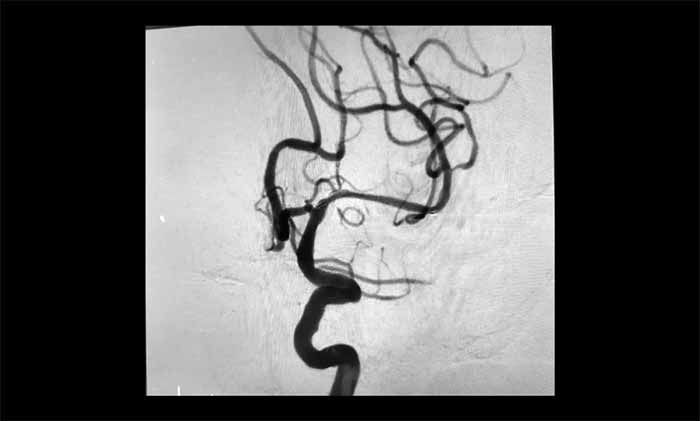

席刚明教授、王贵平博士团队经过全面评估,最终在全麻下精细操作,利用微导丝穿过闭塞段,并以“球囊扩张+支架置入”完成血管再通,为患者打通这条关键的“生命线”。术后患者血流通畅,恢复良好。

▲ 左侧大脑中动脉顺利开通